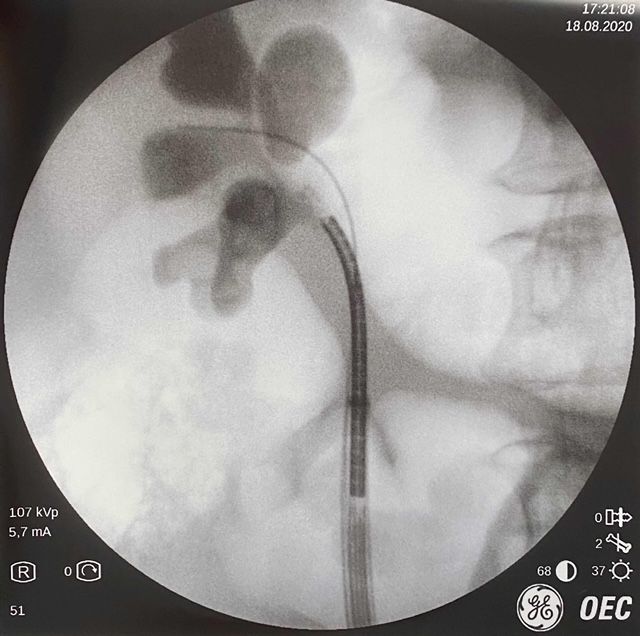

Mi nombre es Miguel Ángel Rodríguez Cabello. Soy médico licenciado por la Universidad de Alcalá y especialista en Urología formado en el Hospital Universitario Ramón y Cajal. Terminé mi formación como especialista en Urología en el año 2015 de la mano de grandes profesionales y maestros, y trato de transmitir todos mi conocimientos y habilidades para el beneficio de mis pacientes. También he completado mi etapa universitaria con el Doctorado, que defendí en la Universidad Autónoma de Madrid en junio de 2023 con resultado Cum Laude. He recibido formación en cirugía robótica (INTUITIVE - DaVinci Xi y SP) en Saint Augustin Clinic de (Burdeos) y estoy acreditado para su utilización por la agencia IRCAD (Strasbourg, France) desde 2017. Tengo amplia experiencia en el manejo de la hiperplasia de próstata con técnicas como la enucleación y vaporización con láser y con la moderna técnica robótica denominada hidroablación - AQUABEAM -, Por último, mi campo de trabajo e investigación más puntera es el diagnóstico y tratamiento del cáncer de próstata (biopsia fusión, terapia focal, prostatectomía radical...), temática que abarca gran parte de mi actividad profesional.

Biopsia de próstata por fusión. Cirugía robótica (DaVinci, AQUABEAM). Cirugía de la hiperplasia de próstata con láser, REZÜM y Aquabeam. Terapia focal en cáncer de próstata (crioterapia, HIFU). Vasectomía sin bisturí. Circuncisión sin bisturí (CIRCURER). Segundas opiniones médicas. Ensayos clínicos en infecciones del tracto urinario.

Tengo un jj desde el jueves y siento molestias al orinar y sangro a veces si a veces no eso es normal?

Buenos días. Completamente normal. Son espasmos, la vejiga y uréter se contraen para intentar expulsar el catéter como "cuerpo extraño" .Trata de relajarte cuando ese dolor empiece, no aguantes demasiado las ganas de orinar, y si no se calma y no tienes alergias a medicamentos, puedes tomar antiespasmódicos tipo buscapina o tamsulosina (repito, siempre que no tenga alergias y bajo supervisión de su urólogo o médico habitual).